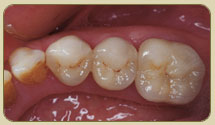

Digital Intra-Oral Camera

If you wish, this useful tool allows you to clearly observe your dental needs prior to treatment, in the planning phase and upon completion of a procedure